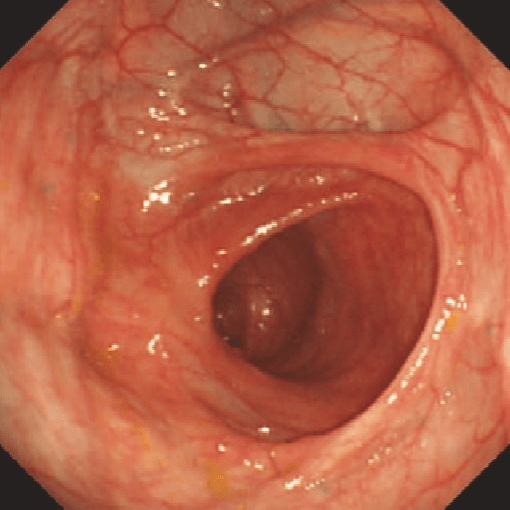

Rutgeerts i0

bolezn_krona.png

i0

Нет признаков воспаления